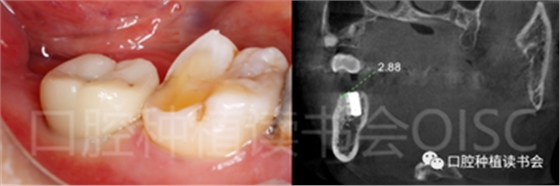

5.4.3 術后第10周,47戴入最終種植冠,X片確認基臺就位準確(圖25),以30N.cm扭矩旋緊基臺螺絲(圖26)。

5.4.4 種植冠封閉螺絲孔后,調(diào)合,拋光,完成最終修復(圖27);戴牙前CBCT顯示:種植體頰側(cè)骨板厚度為2.88mm;47種植冠獲得了良好的穿齦輪廓,并維持了正常的頰側(cè)牙弓輪廓。